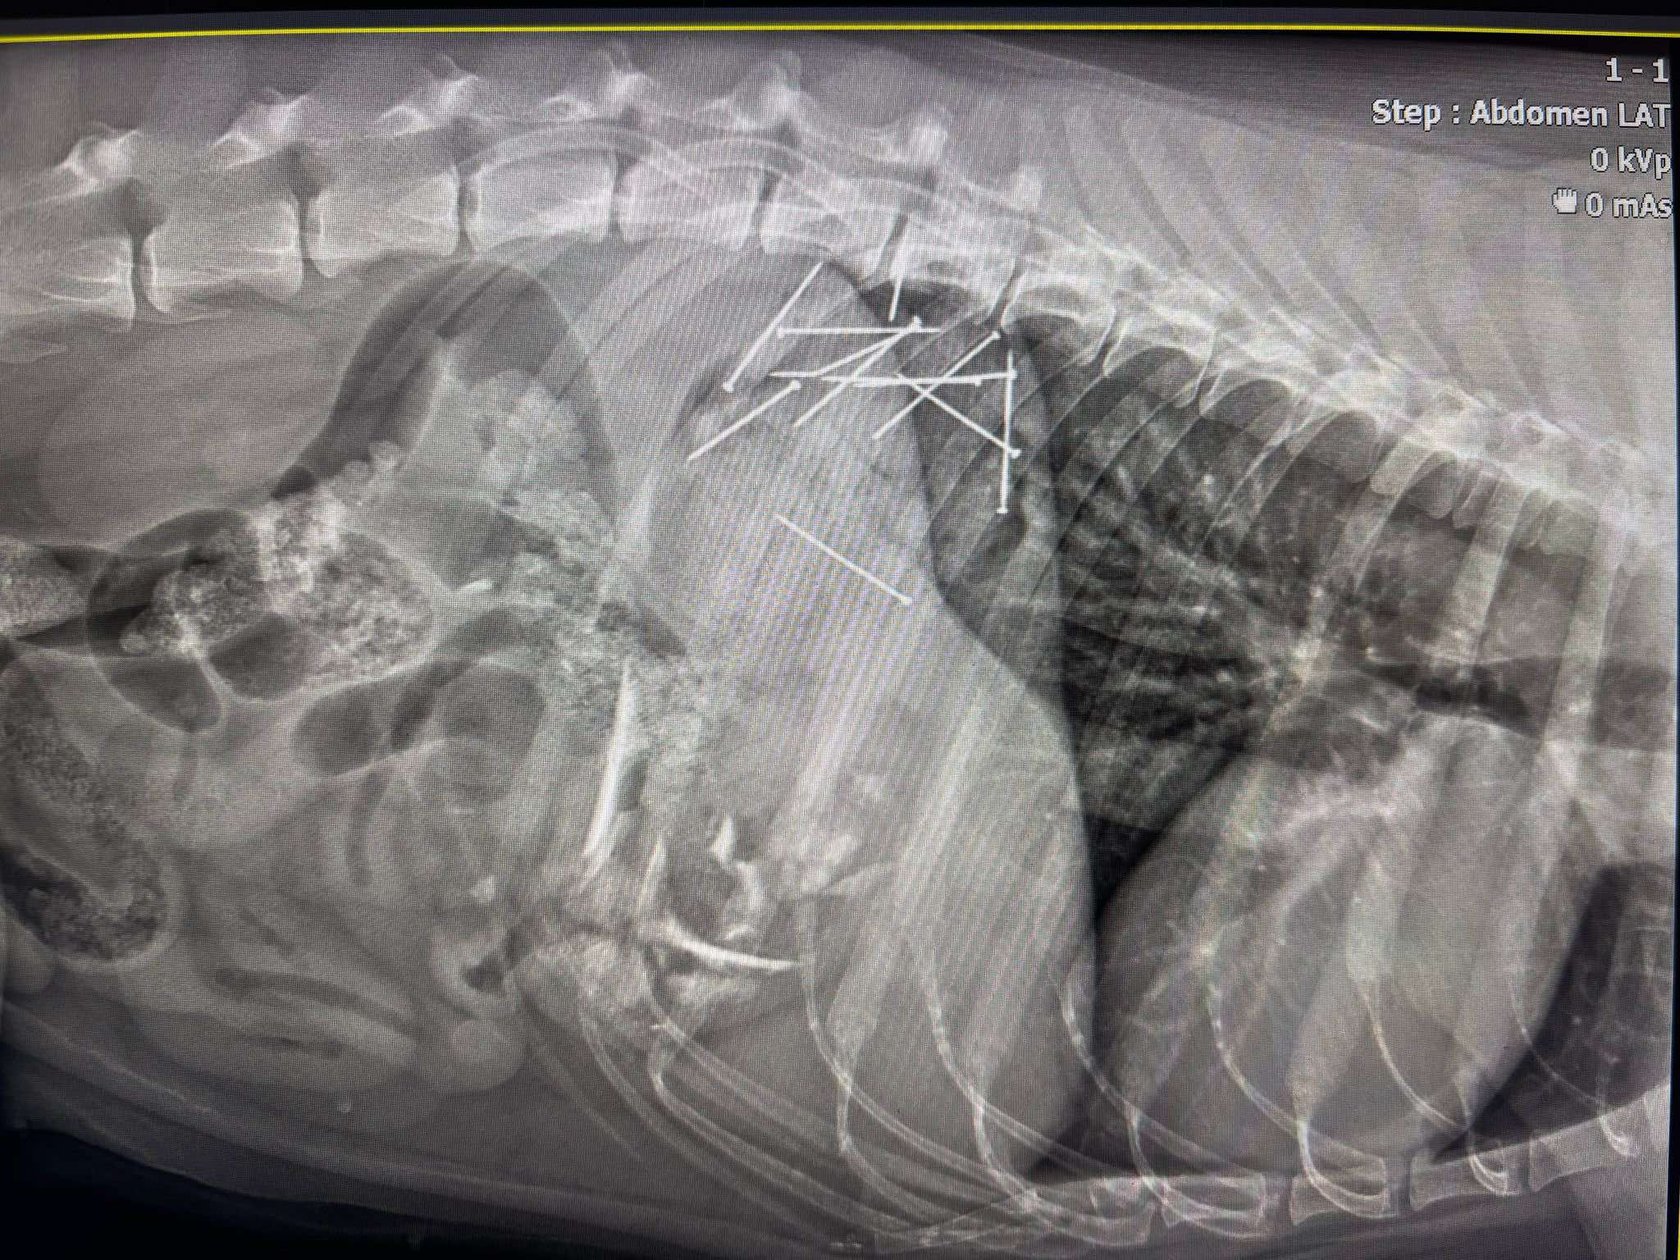

4 / 6 Wróć do artykułu 12 gwoździ wyciągniętych z psiego żołądka 12 gwoździ wyciągniętych z psiego żołądka fot. Stowarzyszenie 4 Łapy Wrocławia Przejdź do poprzedniego zdjęcia. Poprzednie Następne Przejdź do kolejnego zdjęcia. Zdjęcie rentgenowskie psa